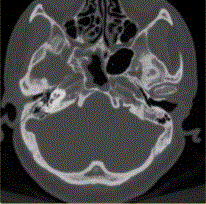

问题 患者男,20岁,外伤后右耳听力下降伴面瘫7d。临床检查,右耳传导性耳聋,发现脑脊液耳瘘。CT表现如下图。 颞骨骨折并发脑脊液耳瘘时应考虑合并

选项 A.鼓室盖断裂、鼓膜撕裂 B.鼓室盖断裂、鼓膜完整 C.前庭导水管断裂、鼓膜撕裂 D.前庭导水管断裂、鼓膜完整 E.咽鼓管断裂

答案 A